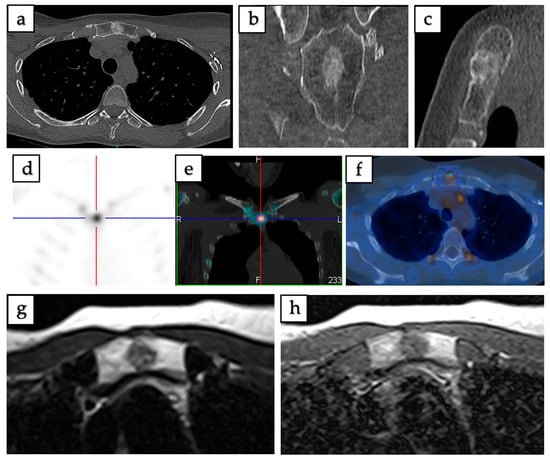

Figure 3. Imaging of intraosseous hibernoma confirmed by biopsy in a 49-year-old female involving the manubrium sterni. (ac) Axial, coronal, and sagittal CT scans demonstrate a well-defined 13 mm sclerotic lesion. (d,e) SPECT-CT reveals increased radiotracer uptake localized to the lesion. (f) 18F-FDG PET/CT shows mild metabolic uptake with a maximum standardized uptake value (SUVmax = 3.2). (g) Axial T1-weighted MRI demonstrates intermediate signal intensity. (h) Axial T2-weighted MRI demonstrates a heterogeneous lesion with mild hyperintensity.

18F-FDG PET/CT (n = 16) revealed increased metabolic activity in 68.75% of cases, with uptake ranging from mild to high. Bone scintigraphy/SPECT (n = 18) demonstrated increased tracer uptake in 72.22%, with limited cases showing no uptake. 68Gallium-DOTATATE PET/CT (68Ga-DOTATATE PET/CT) (n = 4) yielded variable results, with equal distribution among no uptake, mild, moderate, and high uptake categories (25% each), reflecting heterogeneous somatostatin receptor expression. Representative examples of CT, MRI, and PET/CT findings of intraosseous hibernoma are shown in Figure 3 and Figure 4.